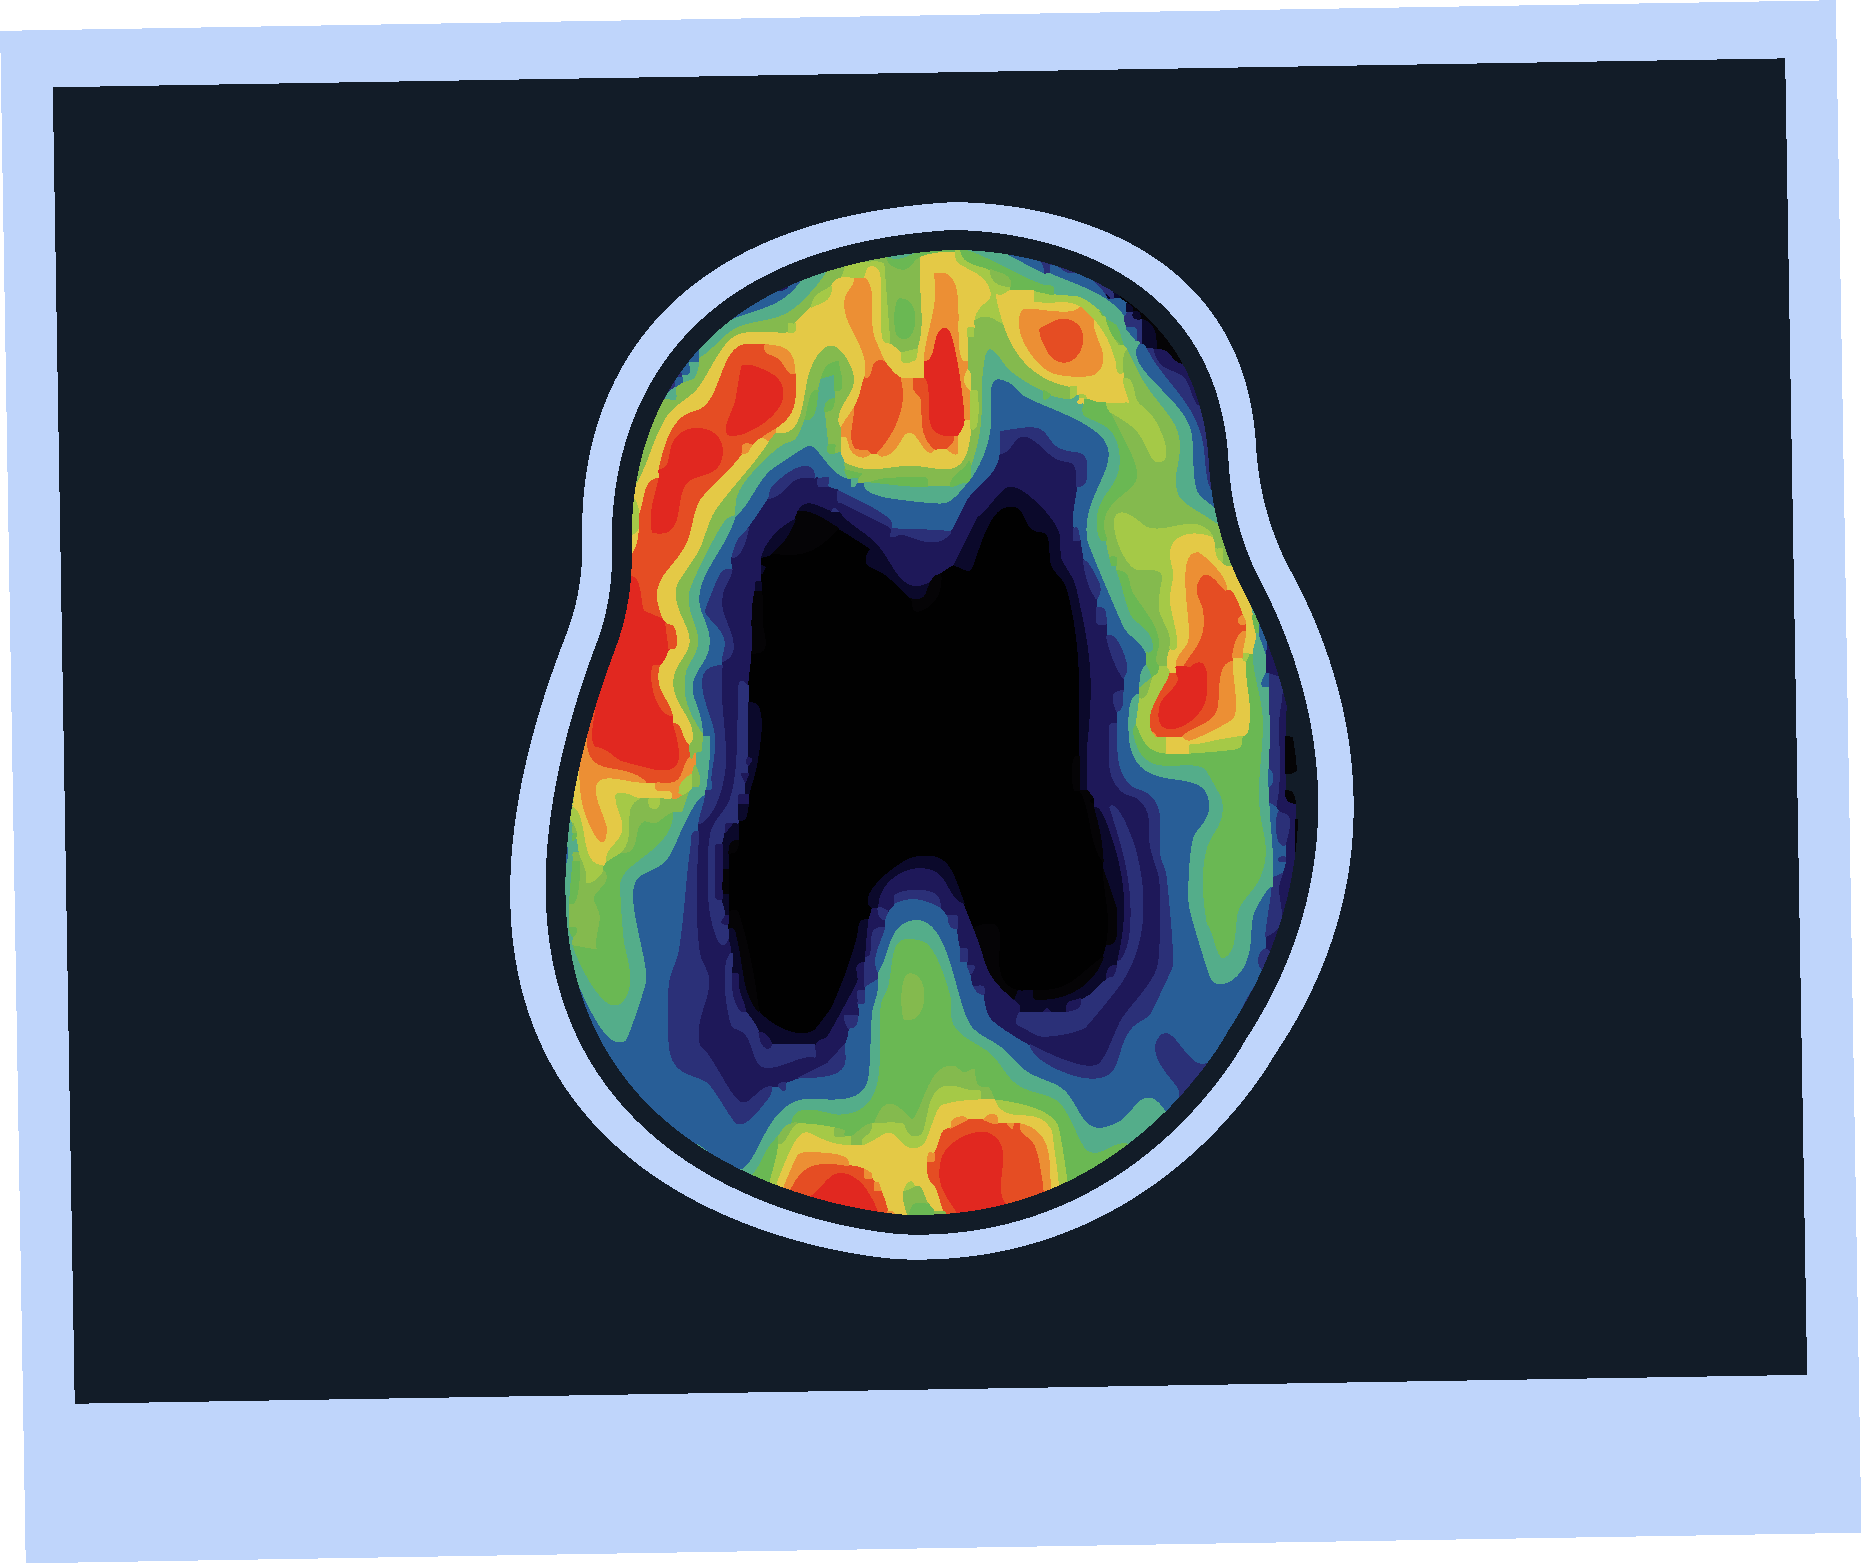

Amyloid PET Imaging

Strengths

Limitations

Sensitivity and specificity >90% for AD pathology.4

FDA approved and 2024 guideline endorsed.5

Minimally invasive.4

Validated versus post-mortem pathology.4

Limited availability.4

Involves radiation exposure.4

Does not assess other causes of cognitive impairment.4

Subject to inter-rater variability.4

Otto lives in a rural area, where PET scans may not be widely available, he may have to travel a long distance to undergo amyloid PET imaging.

One study found that the mean one way travel time to a PET facility was 69 minutes.10